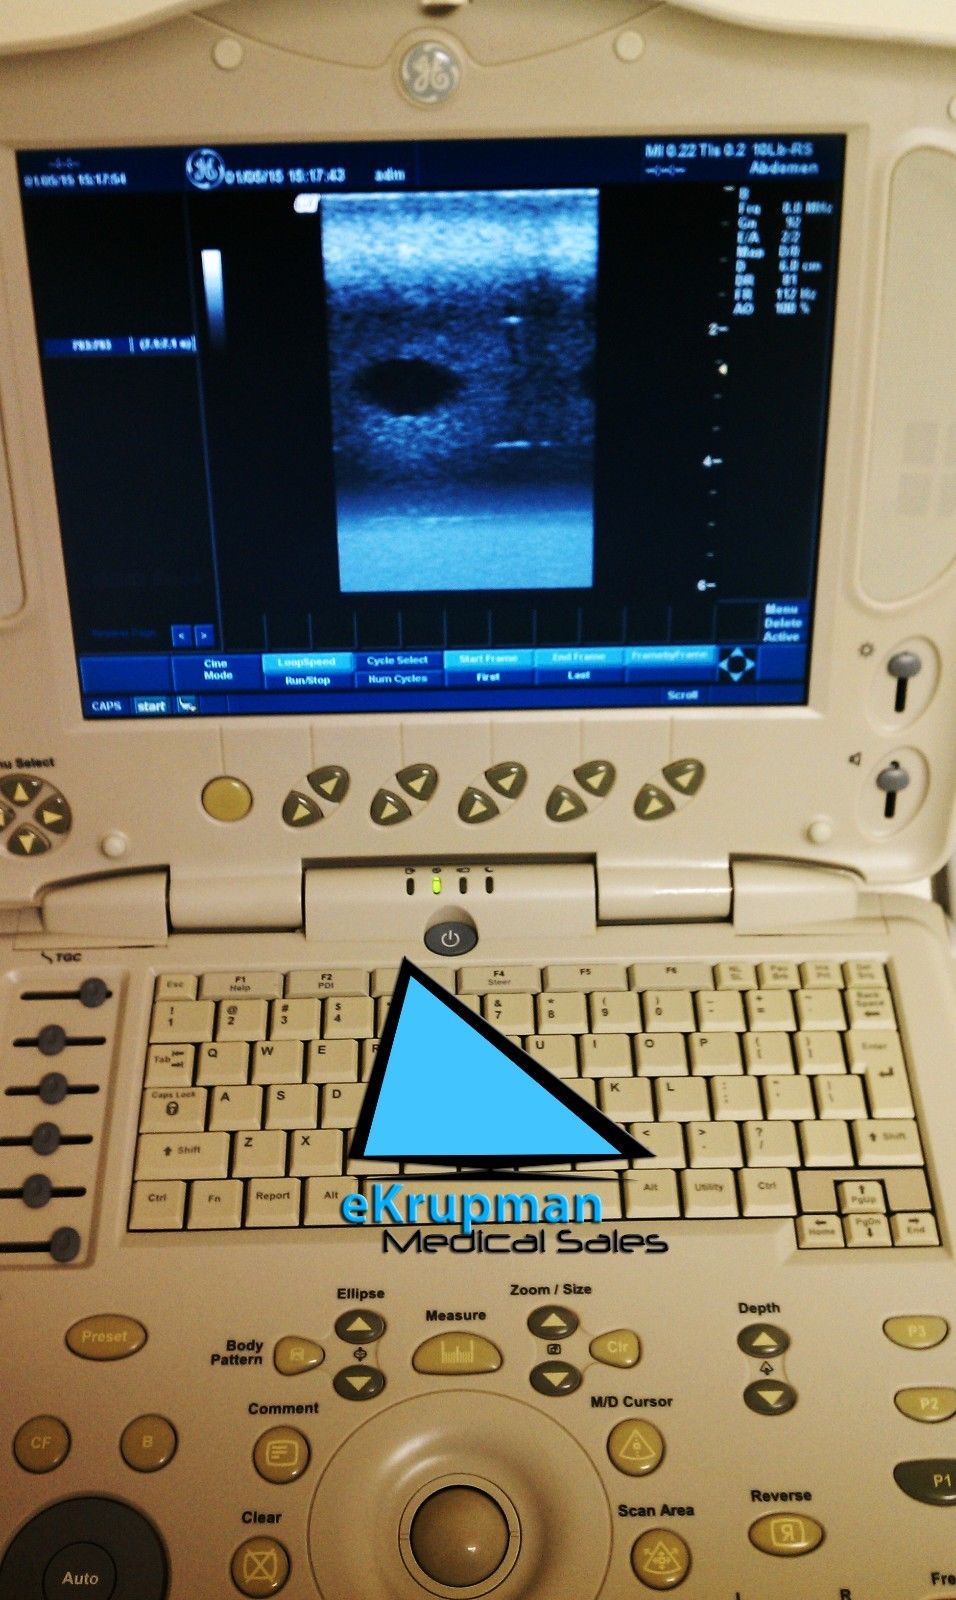

Explore the dependable and sophisticated GE Portable Logiq Book Ultrasound equipped with E8C-RS OB/GYN and 3C-RS Abdominal Transducers. Condition: Gently used with signs of cosmetic wear, yet remains fully operational for accurate diagnostics. Ideal for medical professionals seeking precision with a well-maintained machine. Brand: GE, Model: LOGIQ BOOK. Click to view our detailed listing and invest in advanced medical technology.